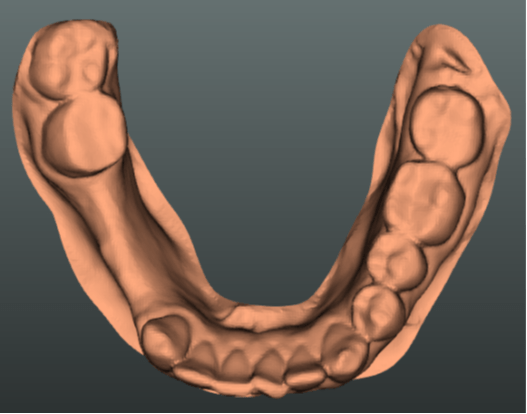

Dental procedures

The total number of dental procedures by a large margin surpasses the total number of other clinical procedures and treatments. Even a small improvement in caries diagnosis accuracy and implantation planning could result in significant savings for the healthcare system. This project aims to develop machine learning solutions for caries and root canal treatment planning.